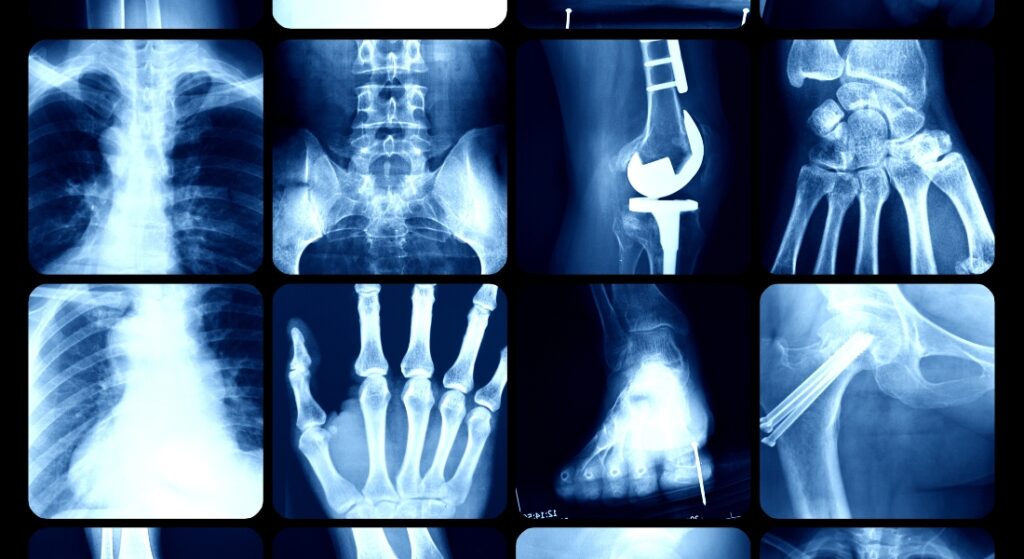

Chụp X-quang (X-ray) là kỹ thuật sử dụng tia X – một loại bức xạ ion hóa – để tạo ra hình ảnh cấu trúc bên trong cơ thể, chủ yếu là xương, khớp và các mô mềm. Khi tia X đi qua cơ thể, chúng sẽ bị hấp thụ khác nhau tùy vào từng loại mô (xương hấp thụ nhiều, mô mềm hấp thụ ít), tạo ra các vùng sáng tối khác biệt trên phim hoặc ảnh kỹ thuật số.

Ngày nay, chụp X-quang không chỉ dừng lại ở xương khớp mà còn được ứng dụng rộng rãi trong các lĩnh vực như:

- Chụp X-quang ngực: phát hiện bệnh phổi, viêm phổi, lao, khối u…

- Chụp X-quang răng: kiểm tra sâu răng, răng mọc lệch, u răng…

- Chụp X-quang ổ bụng, cột sống, khớp gối, khớp háng…